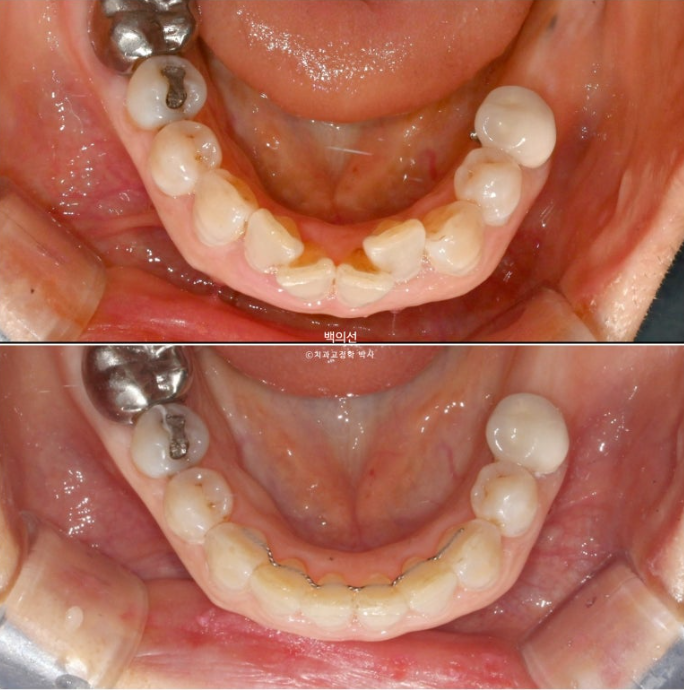

아래 앞니는 치아가 많이 겹쳐져 있습니다.

특히 가운데 앞니와 옆 앞니는 50% 정도가 겹쳐진 상태

치아가 많이 겹쳐진 부위는 가지런히 배열이 끝나면 블랙트라이앵글이 크게 생깁니다.

아래 앞니 배열은 많이 좋아졌으나 아직 배열이 완벽하진 않습니다.

가지런해진 아래 앞니